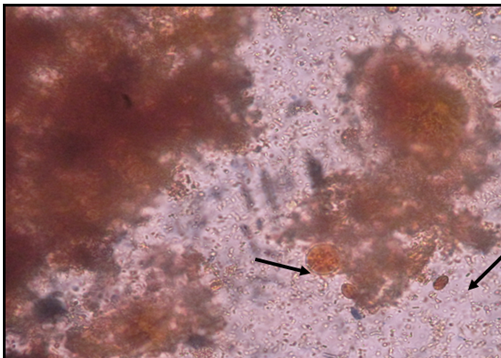

Full history, general examination, random blood sugar test (RBS), Hb and hemoglobin A1c levels were performed for each participant.16 Also demographic data and risk factors for parasitic infections were filled for all participants. Stools samples were obtained from children after the full explanation of the process to them. Fresh faecal samples were collected in dry labeled, plastic containers, with tight fitting covers and they were taken with caution not to be contaminated with urine.5 The samples were transported immediately to the Department of Parasitology zagazig university, where lab assessments were done. Stools samples were examined by direct wet17 and iodine stained smears18 and formol-ether concentration method for the routine screening of ova and parasites diagnostic stages (Figures 1‒10 ).19 Each sample was examined separately. Smears were prepared from sediments of formol-ether concentration for modified ziehl neelsen staining to detect intestinal coccidian and Cryptosporidium spp.19 Slides were examined by light microscopy at ×100, ×400 and ×1000 magnifications. Stools culture on nutrient agar was also done for detection of some intestinal parasites diagnostic stages.20 Patients with T1DM were divided according to the presence or absence of intestinal parasitic diagnostic stages in their stools into two main groups

Figure 8 Lugol’s iodine stained stools smear showing Blastocystis hominis cyst (x400).